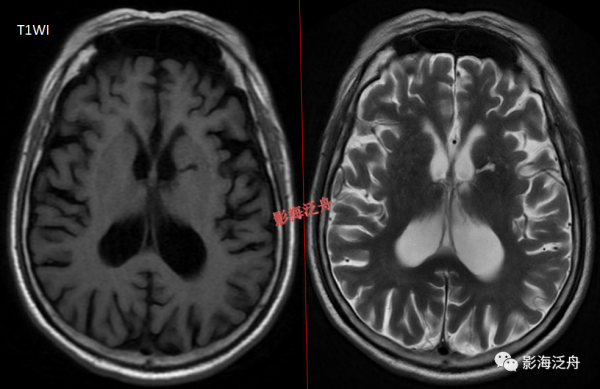

當脫髓鞘改變呈片狀且沿著側腦室周圍對稱性分佈時,大家往往一眼就能識別出來,像上圖這種雙側半卵圓中心多發非特異性脫髓鞘病灶,大家可能就有點心虛了。注意最大的一個病灶(黃箭)長軸平行於側腦室(紅線),所以只是普通的退變,而不是不是MS。

當這種非特異性脫髓鞘病灶比較侷限、散發的時候,如何與VR腔隙及腔梗灶區分呢?一般來說,前者顯示比後兩者更加淺淡和模糊,在T1WI序列尤為明顯。